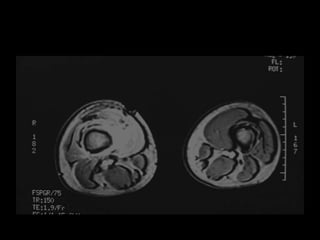

• MRI is superior in the assessment of a soft tissue

mass.

MRI

Visualize entire bone and adjacent joint

Best test for intraosseous extent and soft tissue

extent

Identify skip metastases

Tumor proximity to neurovascular structures

Occasionally helpful in diagnosis of bone or soft

tissue tumors (experienced radiologist)